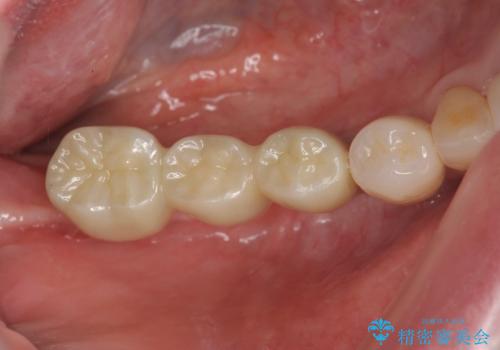

歯周病で失った歯をインプラント治療で咬合機能回復

奥歯を多数失い全く噛めない期間があり、困り果てて来院されましたが、インプラント治療をおこなったことでしっかりと噛めることができるようになりまた食事を楽しめるようになったと大変喜んでいただくことができました。